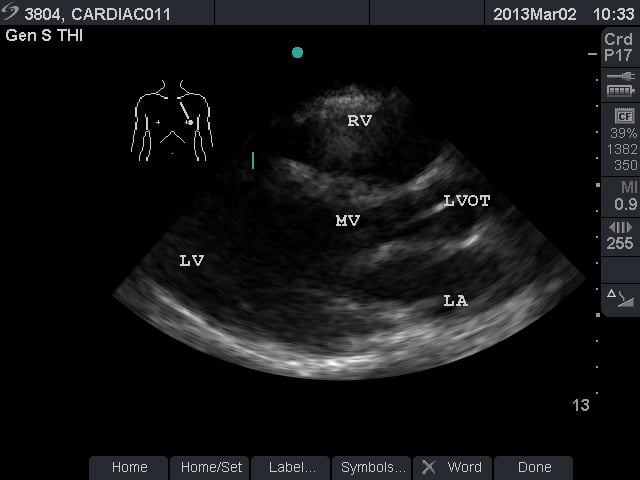

Video 1. Normal Subxiphoid View - Parasternal Long Axis View: This view captures the flow of blood through the left side of the heart. The apex is to the left of the screen. The mitral valve leaflets are seen and often chordae tendinae connecting them to papillary muscles. Two cusps of the aortic valve (usually the non-coronary and right coronary cusp) are seen. The left ventricular outflow tract (LVOT) is the term for the aortic root and proximal ascending aorta. A portion of the right ventricle is seen in the near field.

- Figure 2. Parasternal long axis view. RV = Right ventricle. LV = left ventricle. MV = mitral valve. LVOT = left ventricular outflow tract. LA = left atrium